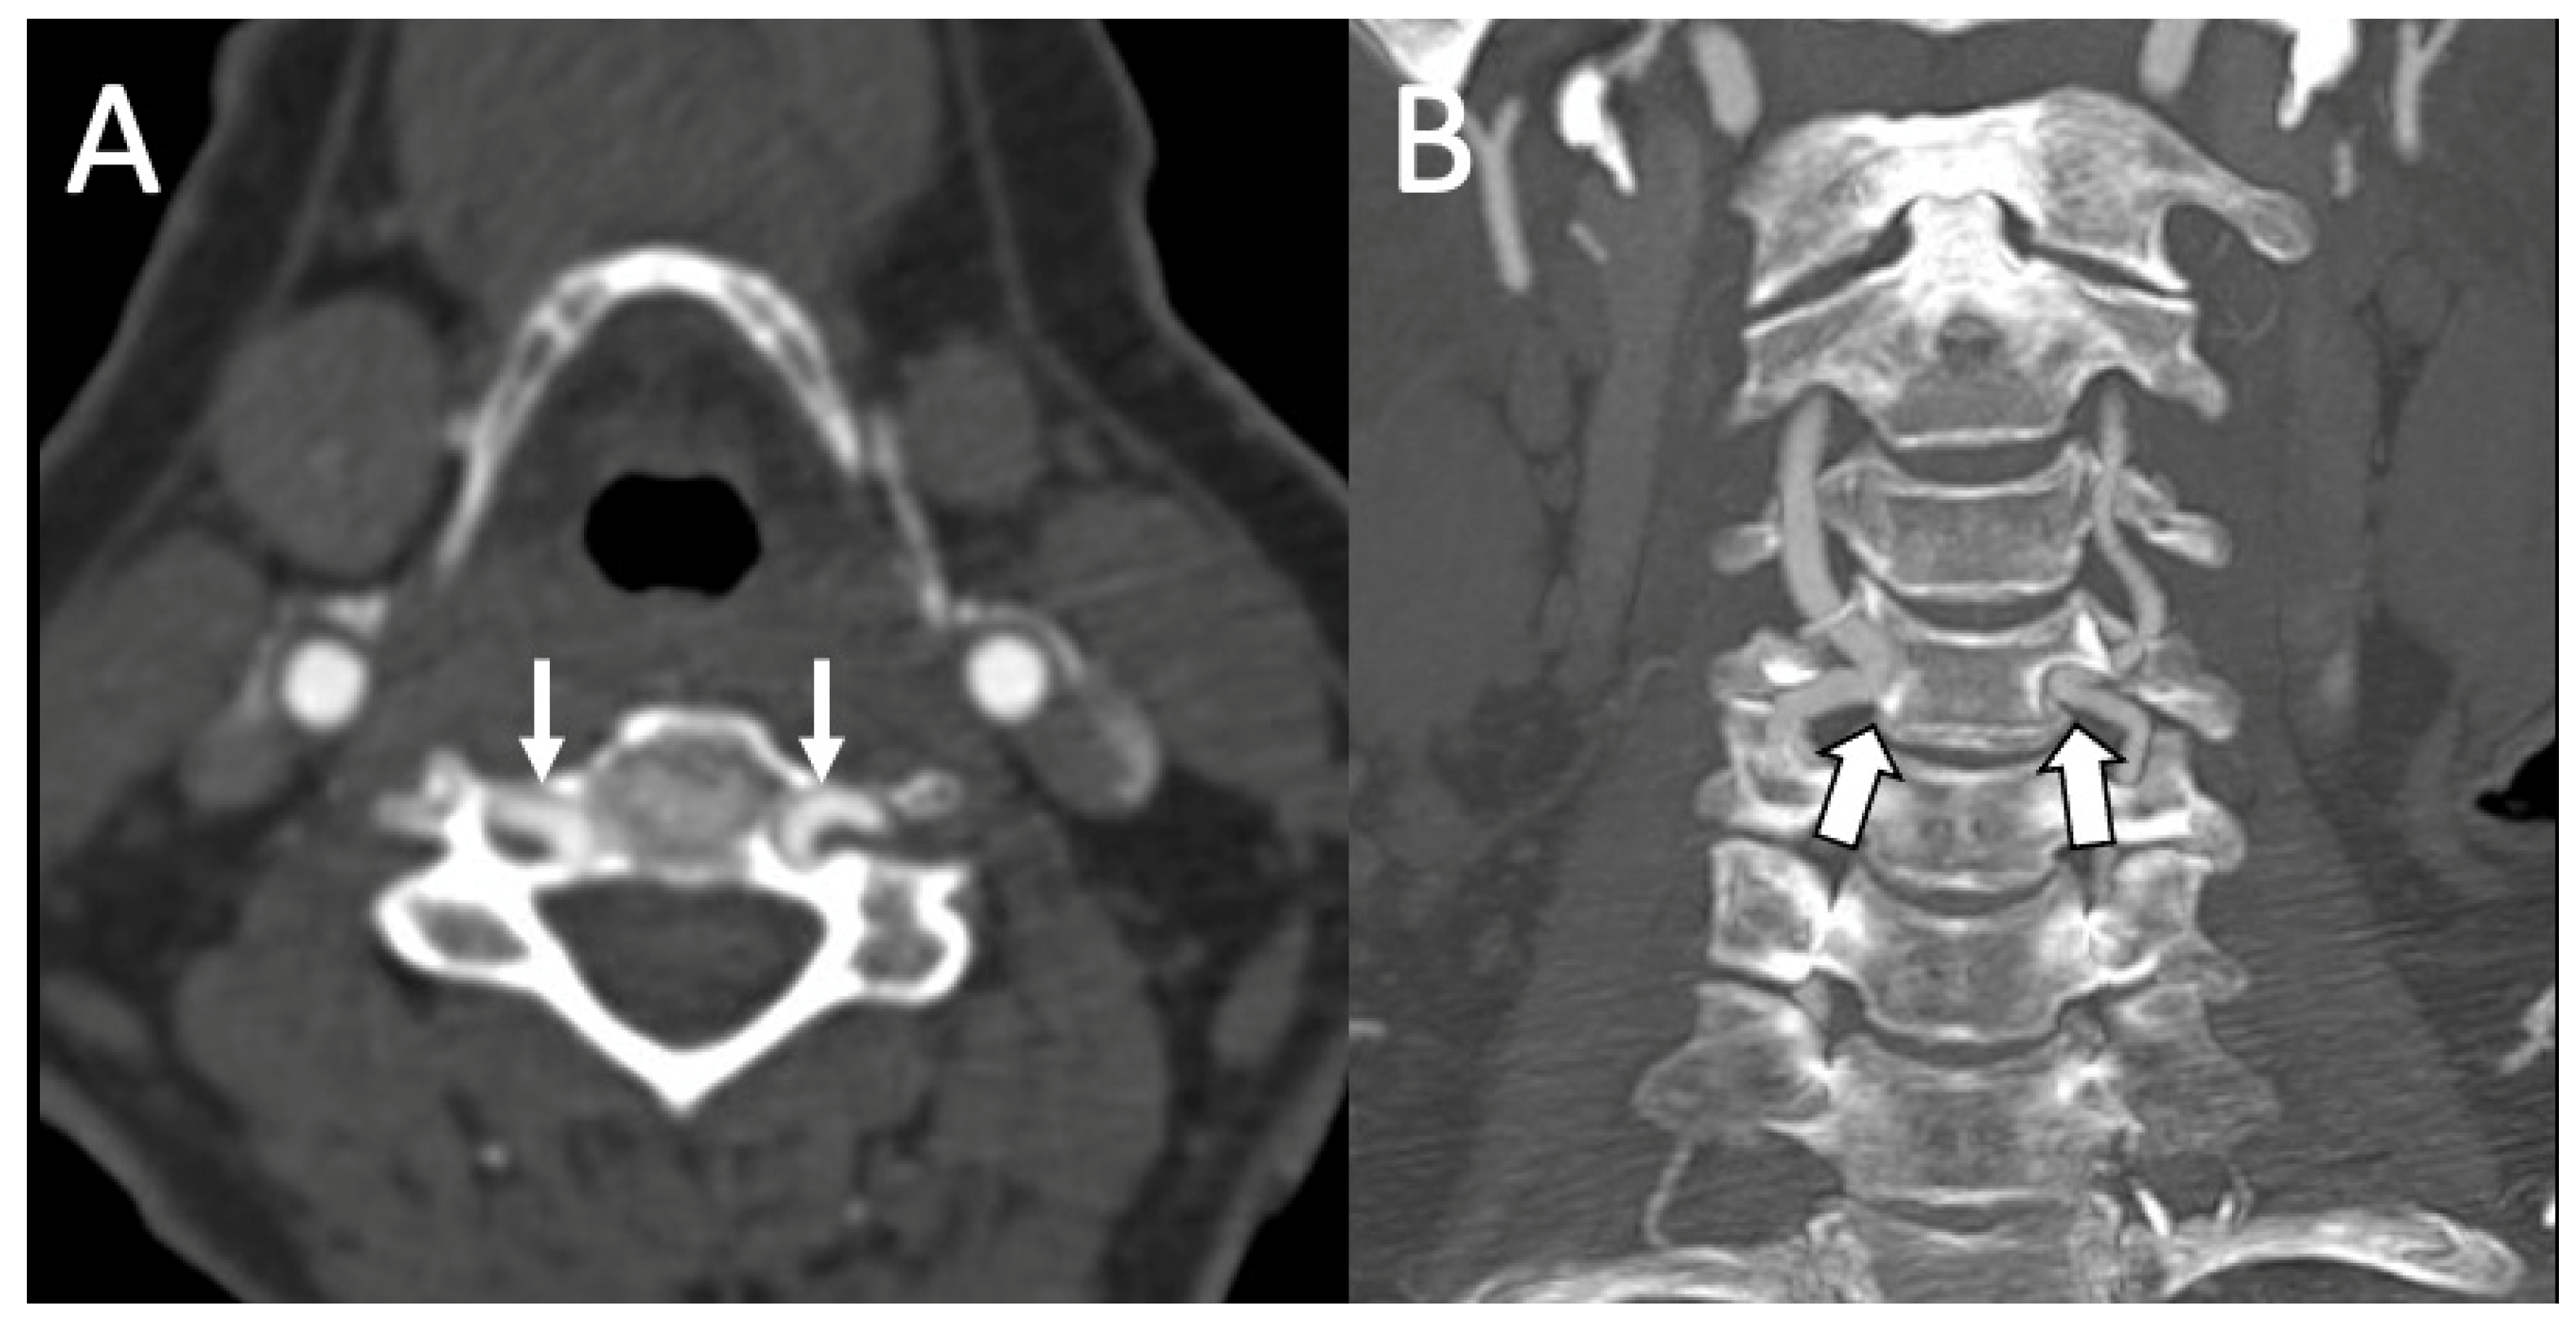

3.1. Variations in the V2 Segment